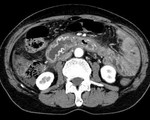

[画像診断]胆嚢捻転症、CT所見について 2011-04-12